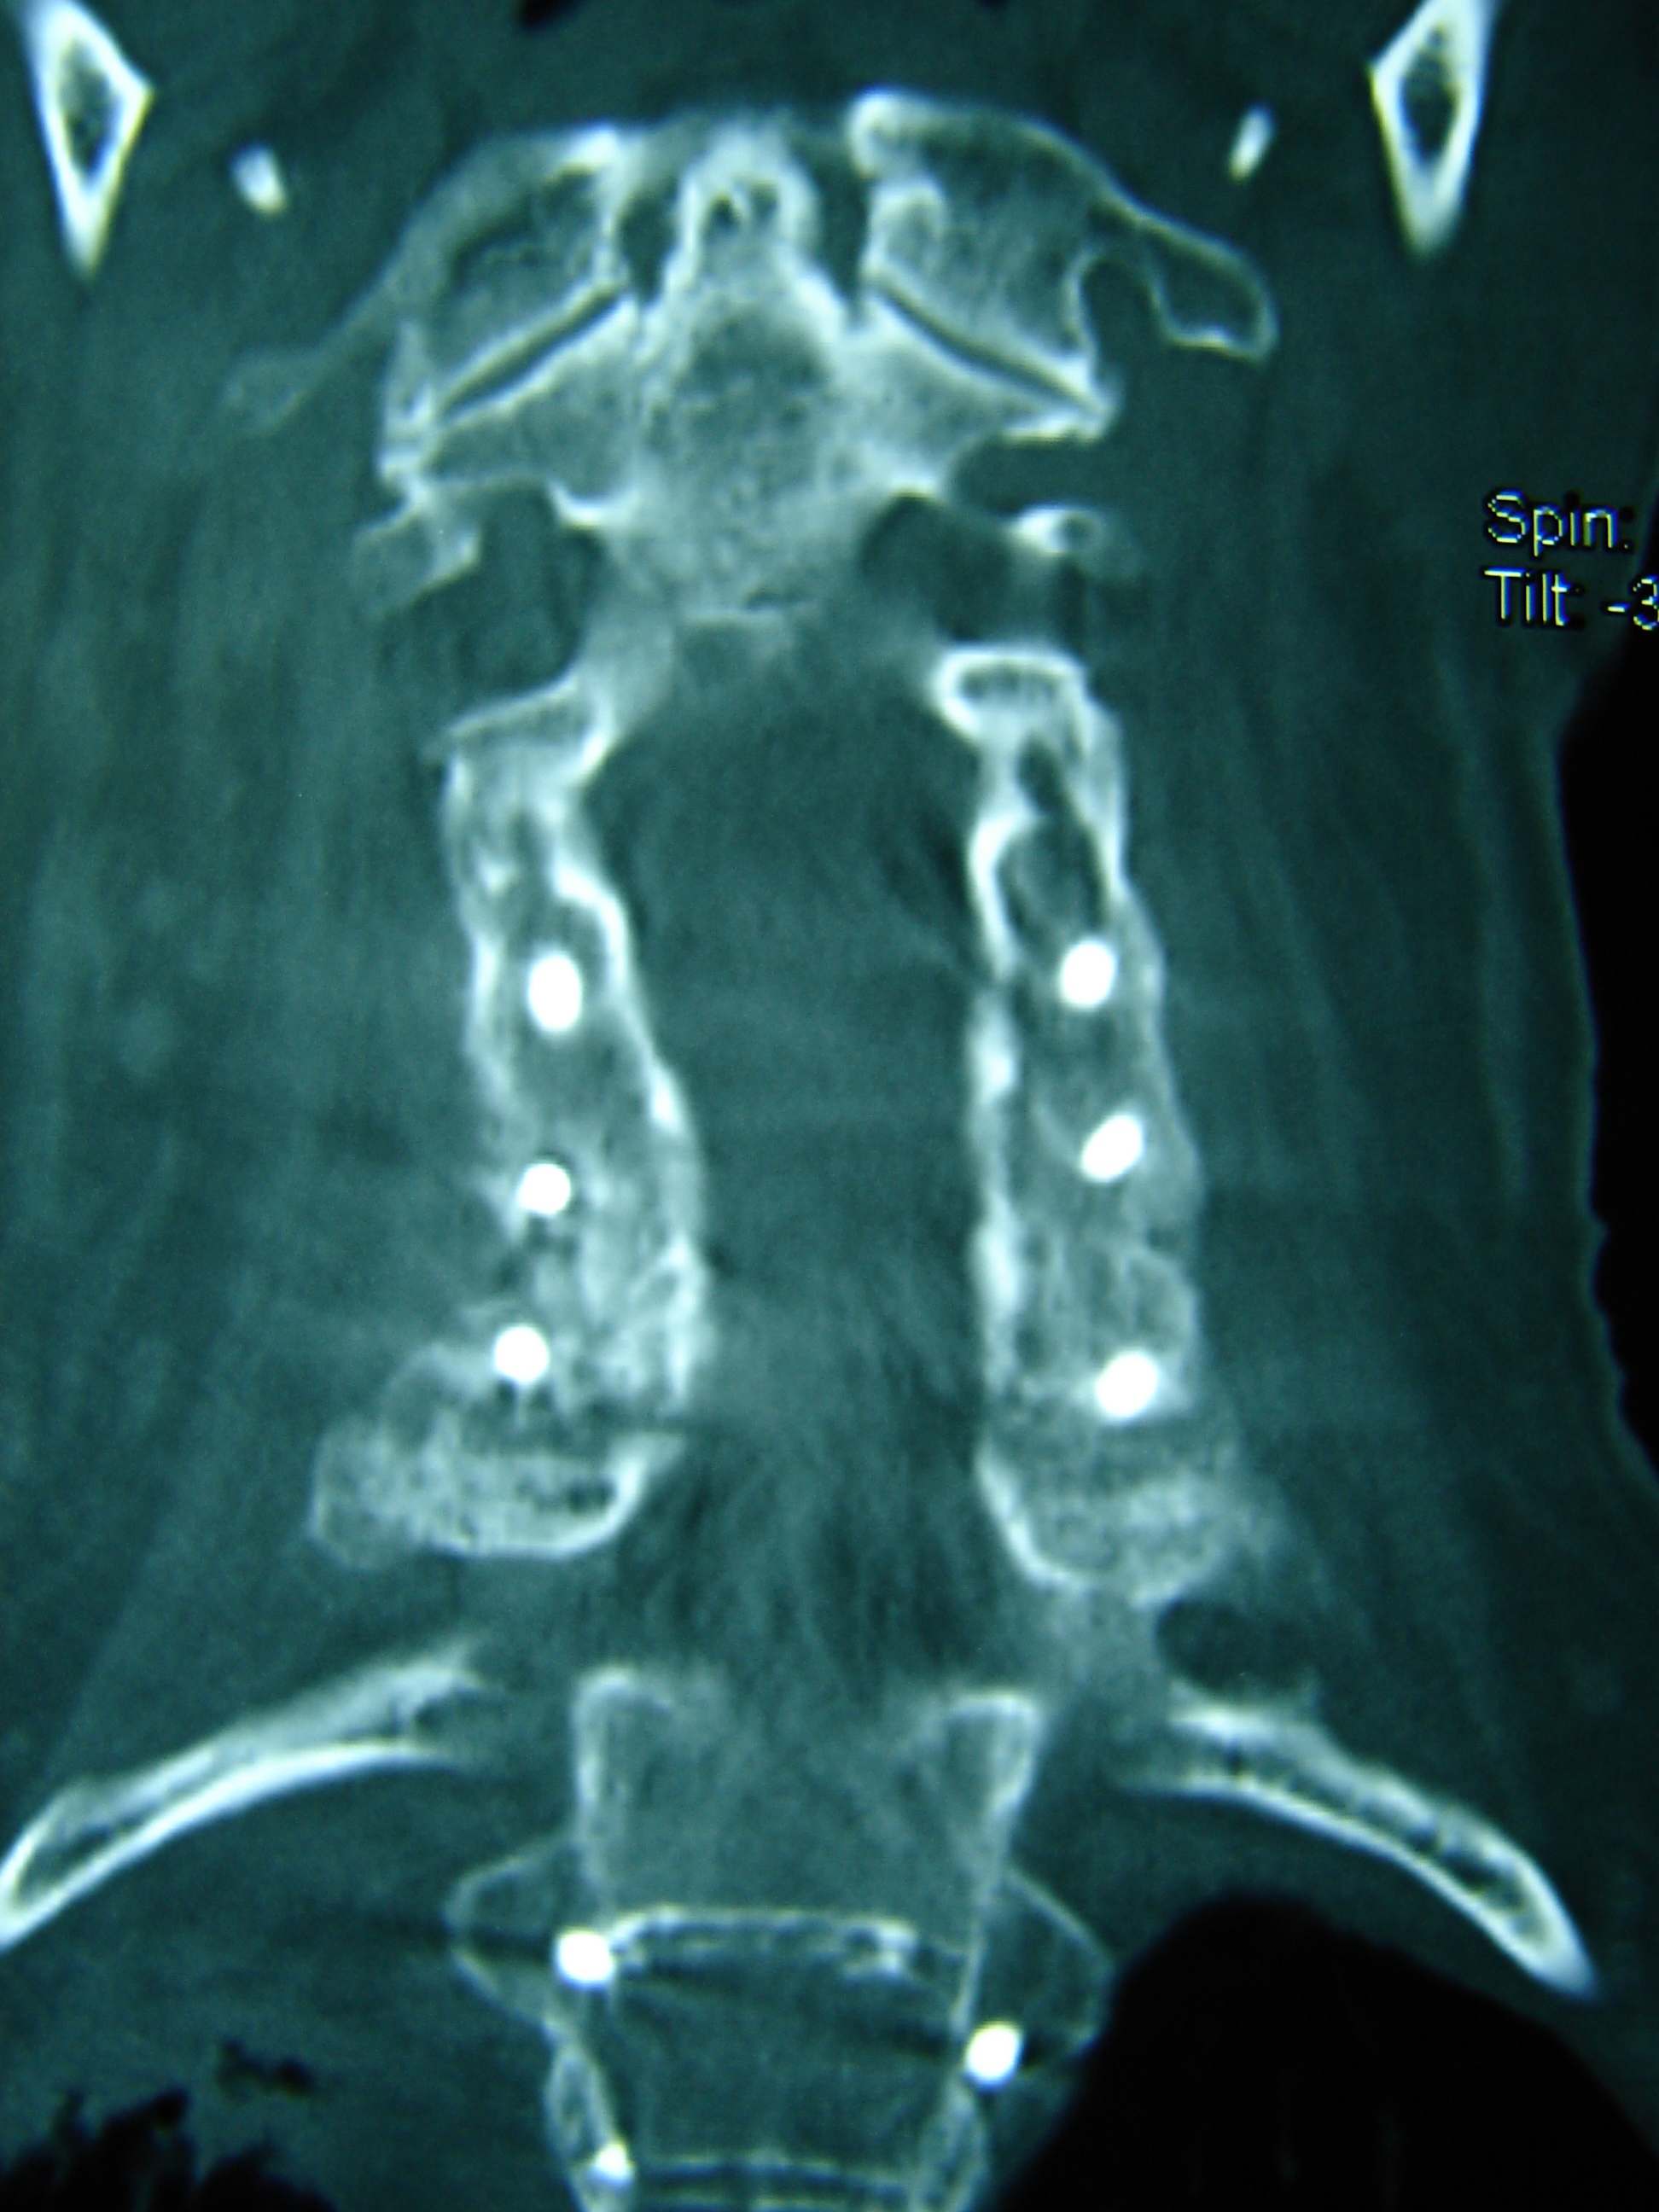

Εικόνα 8 – Μετεγχειριτική αξονική τομογραφία Α.Μ.Σ.Σ.

α,β Οβελιαία λήψη

γ,δ Μετωπιαία λήψη

Παρατηρείται η ανάταξη και καλή σταθεροποίηση της Α.Μ.Σ.Σ. με σύστηματα σταθεροποιήσεως προσθίας και οπισθίας.